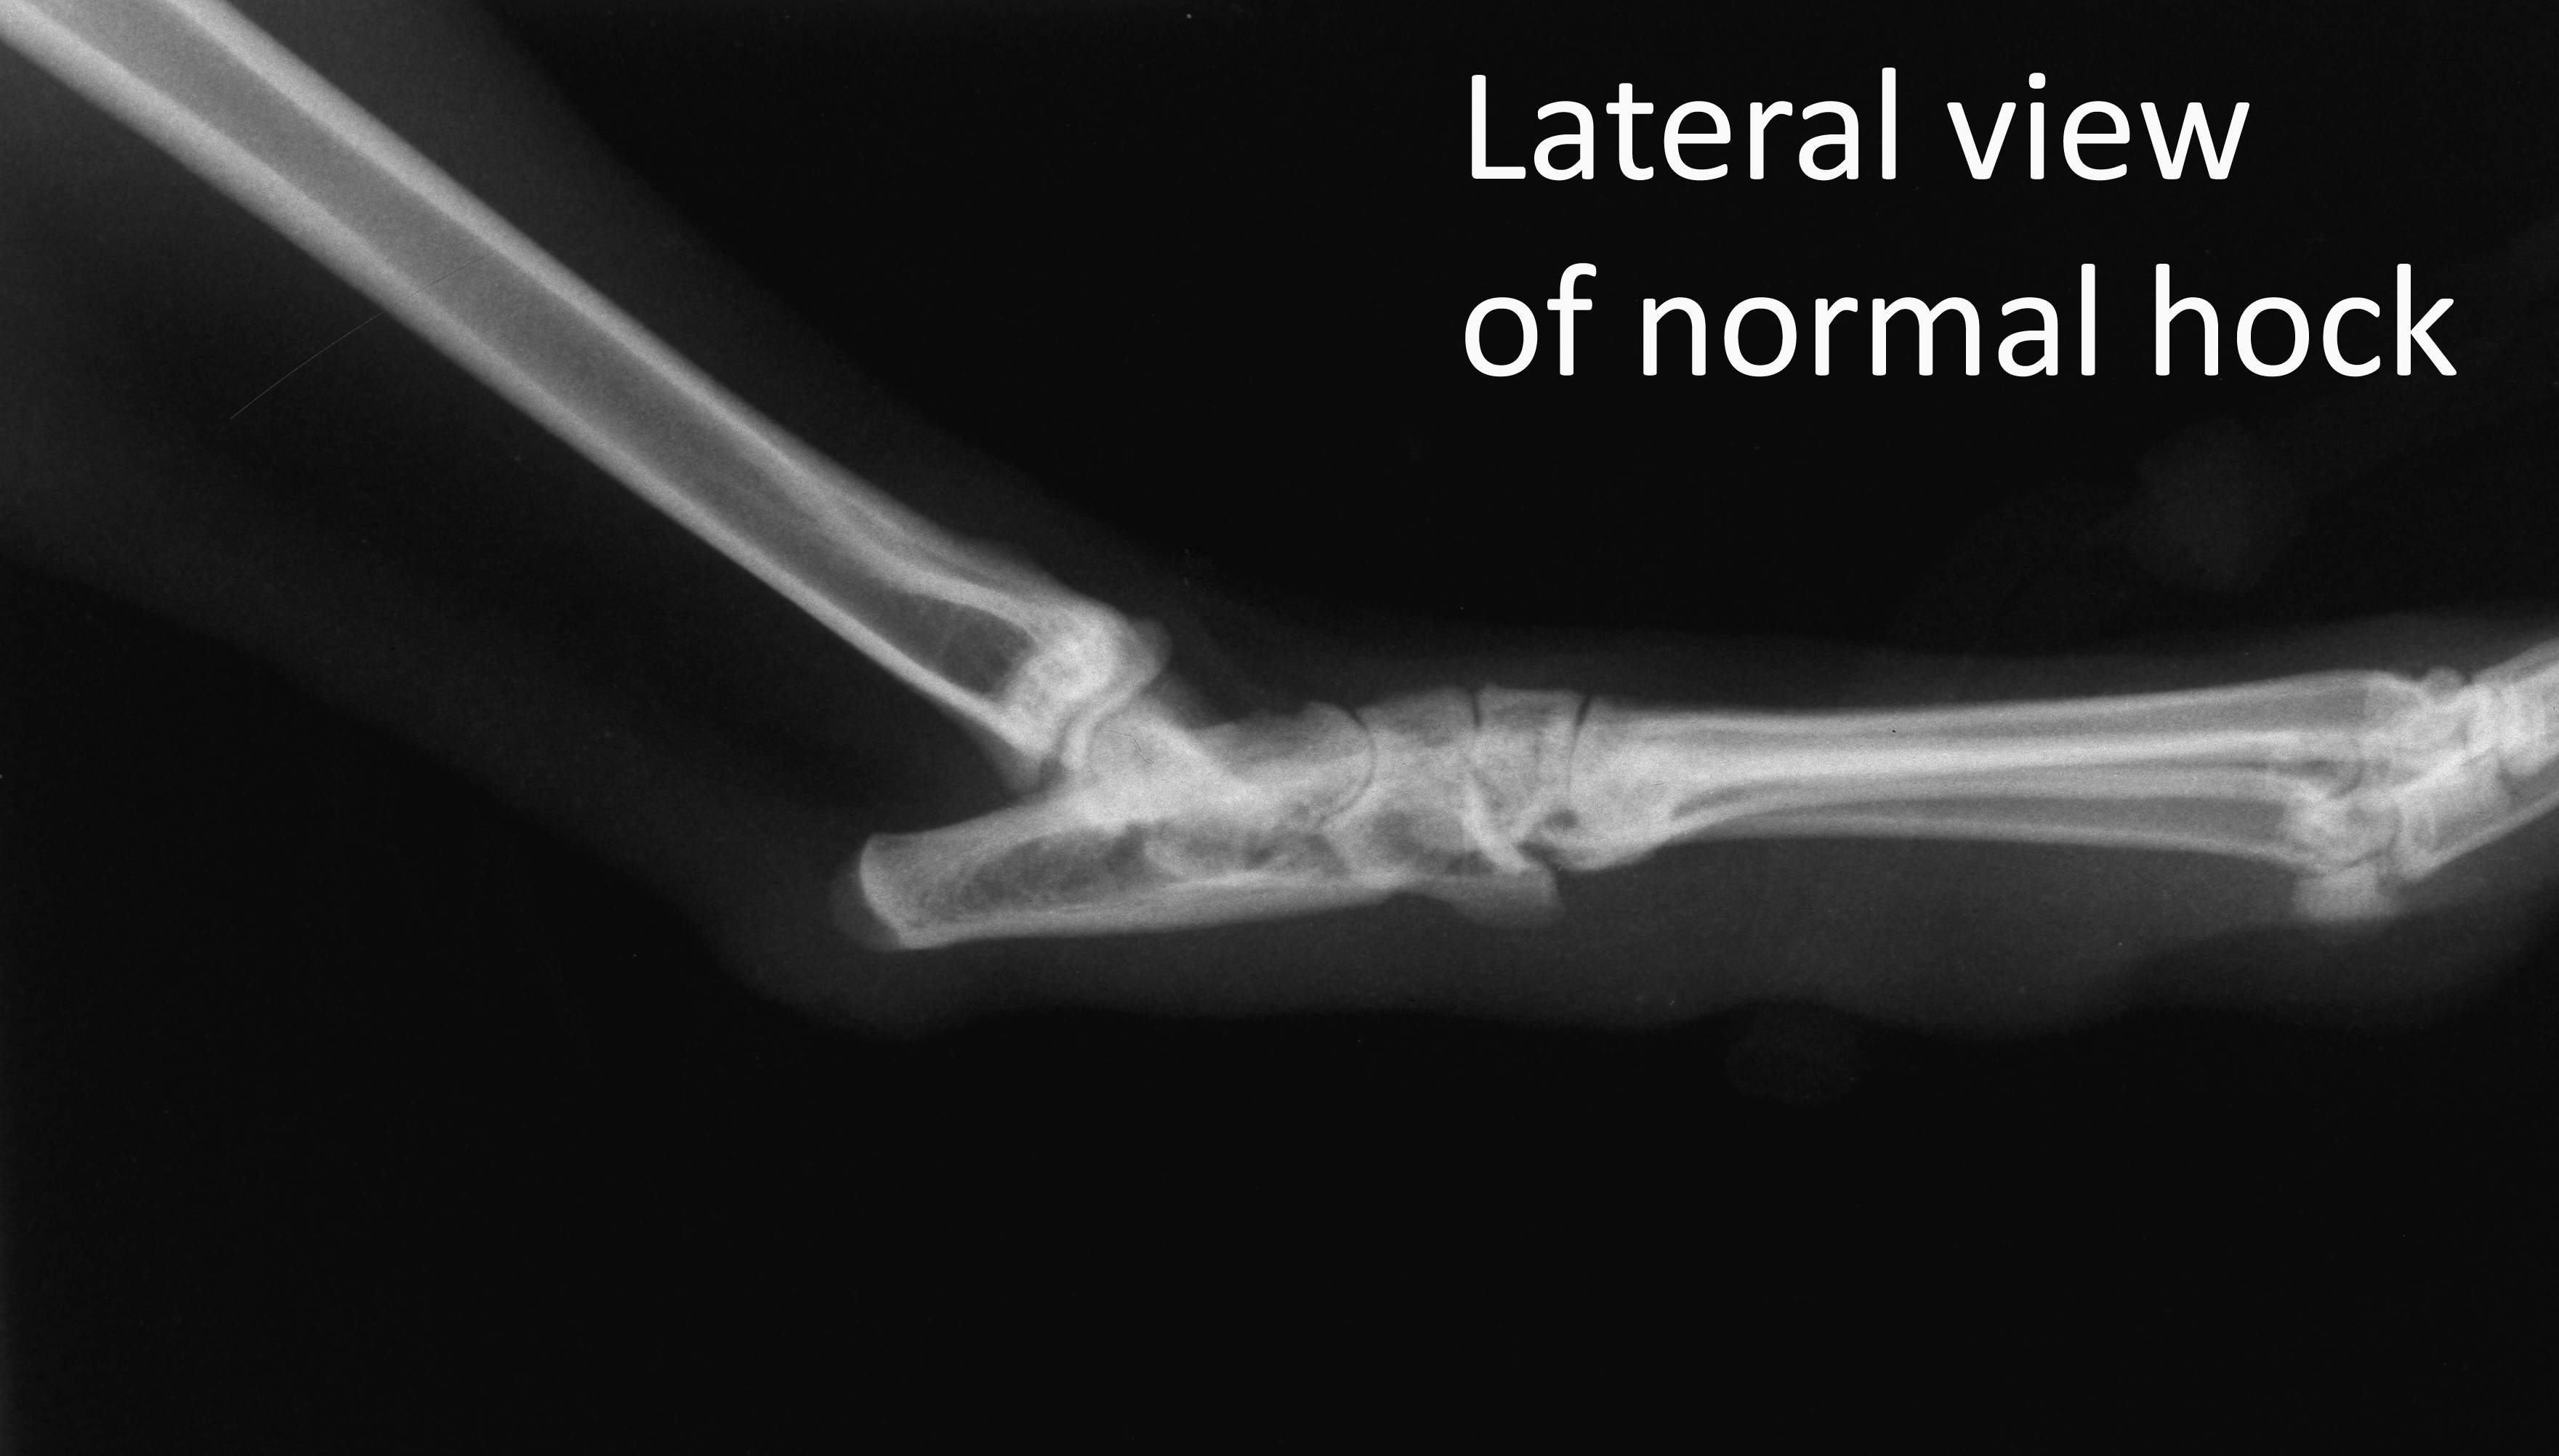

Lateral view of normal hock

Radiograph

Orthopaedics